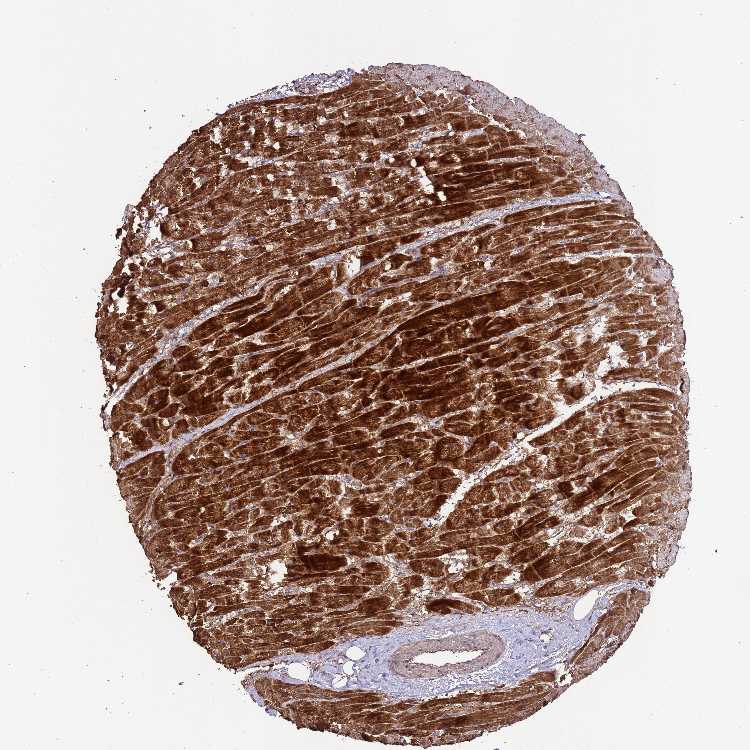

TISSUE PRIMARY DATA HEART MUSCLE Show tissue menu

HEART MUSCLE - Antibody stainingi

Antibody staining in the annotated cell types in the current human tissue is reported as not detected, low, medium, or high, based on conventional immunohistochemistry profiling in selected tissues. This score is based on the combination of the staining intensity and fraction of stained cells.

Each image is clickable and will lead to virtual microscopy that enables deeper exploration of all samples and also displays staining intensity scores, fraction scores and subcellular localization as well as patient and tissue information for each sample.

Antibody HPA044930

Cardiomyocytes High